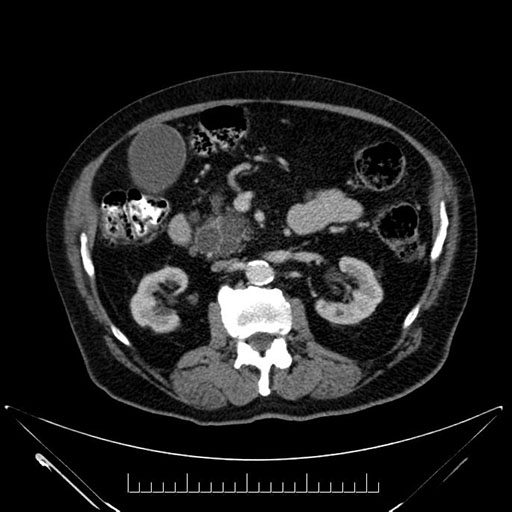

Whipple (pancreaticoduodenectomy) [case 7]

Imaging Analysis

Look through the patient's CT scan to identify any areas of concern for the necessary procedure.

Axial - 3 months prior